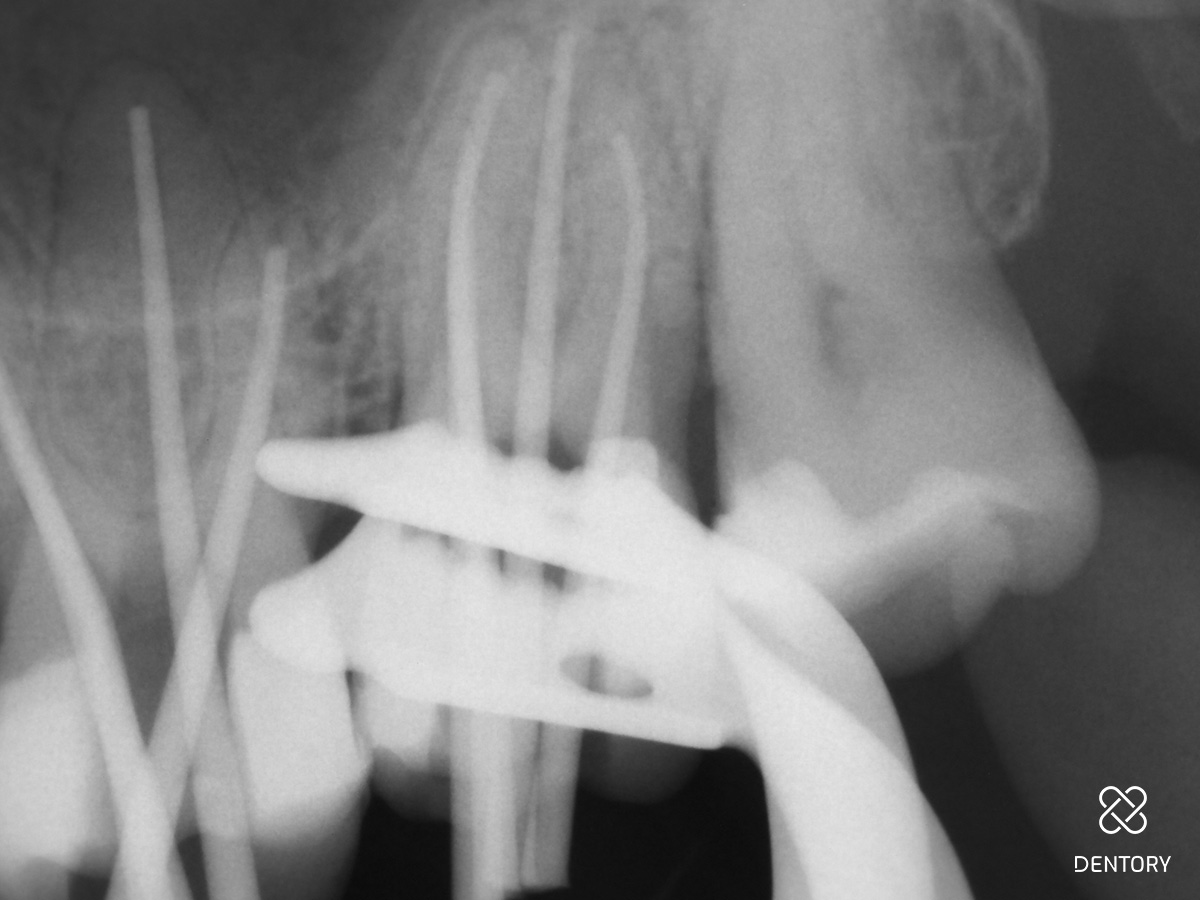

Abbildung 2

Röntgenologische Ausgangssituation.